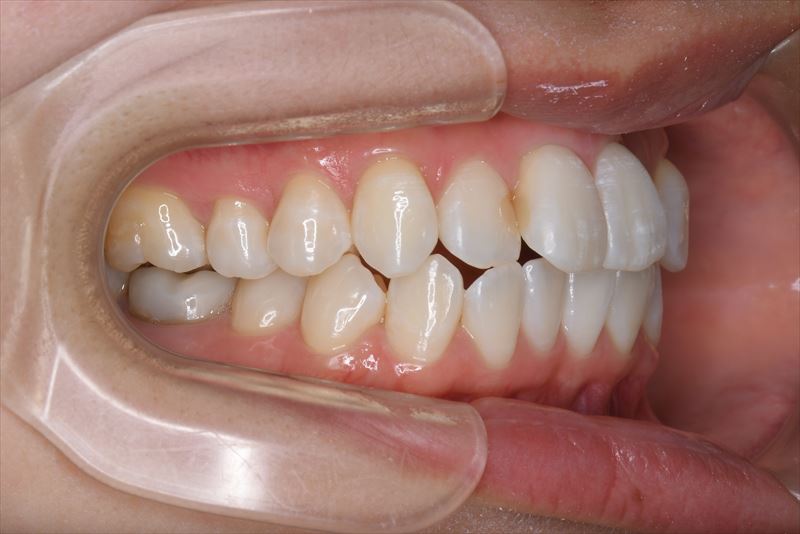

治療中